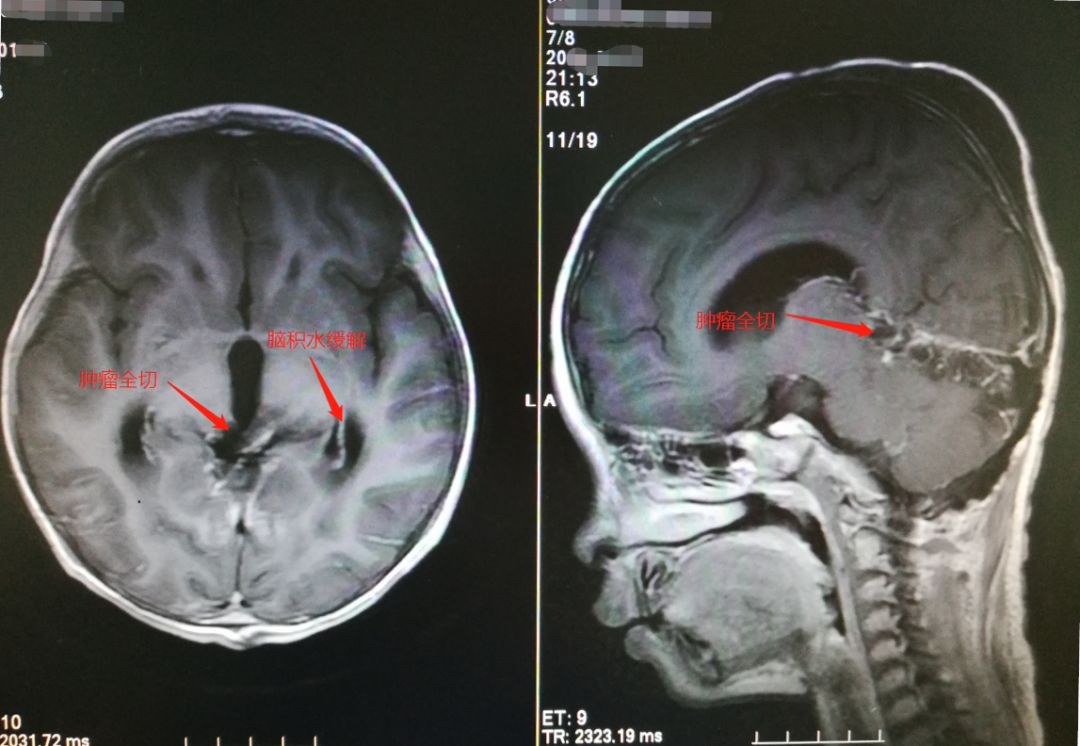

▲患儿术后复查MR

1月15日,鲁明团队在神经内镜下为患儿实施了松果体占位性病变切除术,成功从患儿颅内切除了一个含有5颗“牙齿”和“毛发”的肿瘤。术后病理报告提示为畸胎瘤,证实了鲁明的术前诊断。